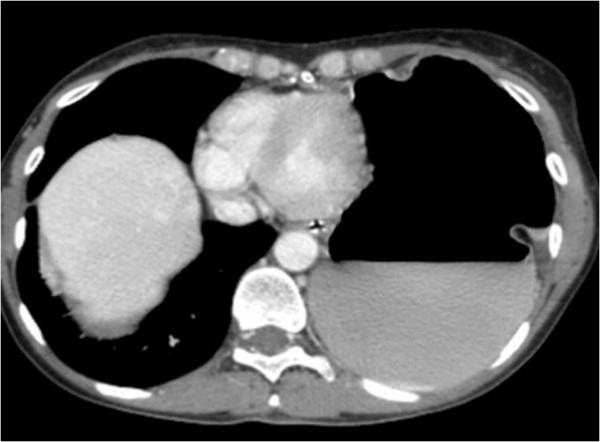

Patients with extensive peritoneal spread from advanced ovarian cancer often undergo several upper abdominal surgical procedures including subphrenic peritonectomy to obtain optimal cytoreduction. The most common complications are pleural effusions, pancreatic leakage and endoabdominal collections. This case report describes an unusual complication, a diaphragmatic hernia with an intrathoracic gastric volvulus developing four months after the patient underwent left subphrenic peritonectomy during interval debulking surgery and hyperthermic intraperitoneal chemotherapy for advanced ovarian cancer.

患有晚期卵巢癌广泛腹膜播散的患者通常需要进行多次上腹部手术,包括膈下腹膜切除术,以获得最佳的减瘤效果。最常见的并发症是胸腔积液、胰漏和腹腔内脓肿。本病例报告描述了一种罕见的并发症,即在接受左膈下腹膜切除术和腹腔内热灌注化疗治疗晚期卵巢癌的间隔减瘤手术后四个月,发生了膈疝和胸腔内胃扭转。